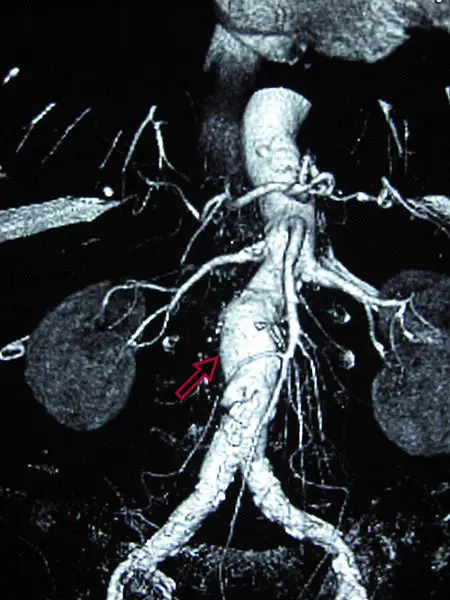

Abdominal Aortic Aneurysm

Abdominal aortic aneurysm (AAA) is an aneurysm of the abdominal aorta.

Abdominal aortic aneurysm typically develops above the aortic bifurcation but below the renal arteries.

Abdominal aortic aneurysm (AAA) is typically associated with hypertension and atherosclerosis.

Atherosclerosis causes the vessel wall to atrophy and become weaker by raising the diffusion barrier to the media.

Complications of abdominal aortic aneurysm (AAA) include:

- Rupture, especially when the diameter is greater than 5 cm

- Compression of nearby structures (such as the ureter)

- Thrombosis

- Embolism